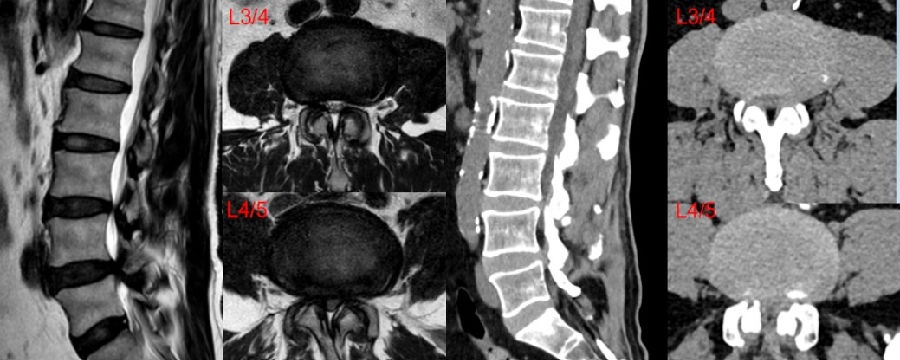

八、医源性不稳定(0.88%)

发生率0.6%,明显低于开放式手术,小关节突关节损伤是主要原因。上腰椎(L1~L3)病变、存在狭窄椎板和脊柱矢状面失衡的患者减压过程几率更高。

病例(关节突损伤)

男,52岁。

主诉:腰痛20余年,双下肢疼痛10余年,加重4天。

查体:双侧直腿抬高试验及加强试验(-),双侧膝腱反射及跟腱反射未引出,Babinski征(-)。

思考及建议

使用磨钻从棘突基底部与上椎板下缘交界处切开

术前CT测量关节突切除范围

L3-4及以上节段,对侧入路切除椎间盘